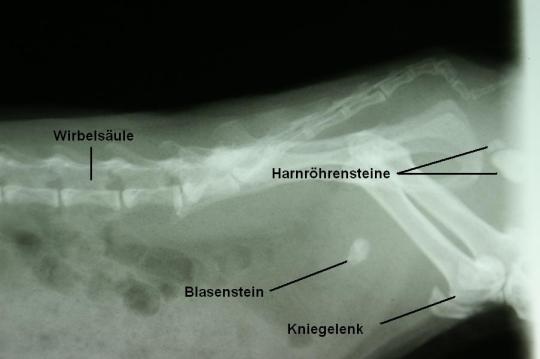

Eine seitliche Röntgenaufnahme des Bauches wird angefertigt. Dabei wird ersichtlich, dass „Lois“ nicht nur einen Blasenstein, sondern offenbar auch 2 Harnröhrensteine aufweist. Diese Fremdkörper bewirken eine Entzündung und Reizung von Blase und Harnröhre, welche den blutigen Urin erklären.